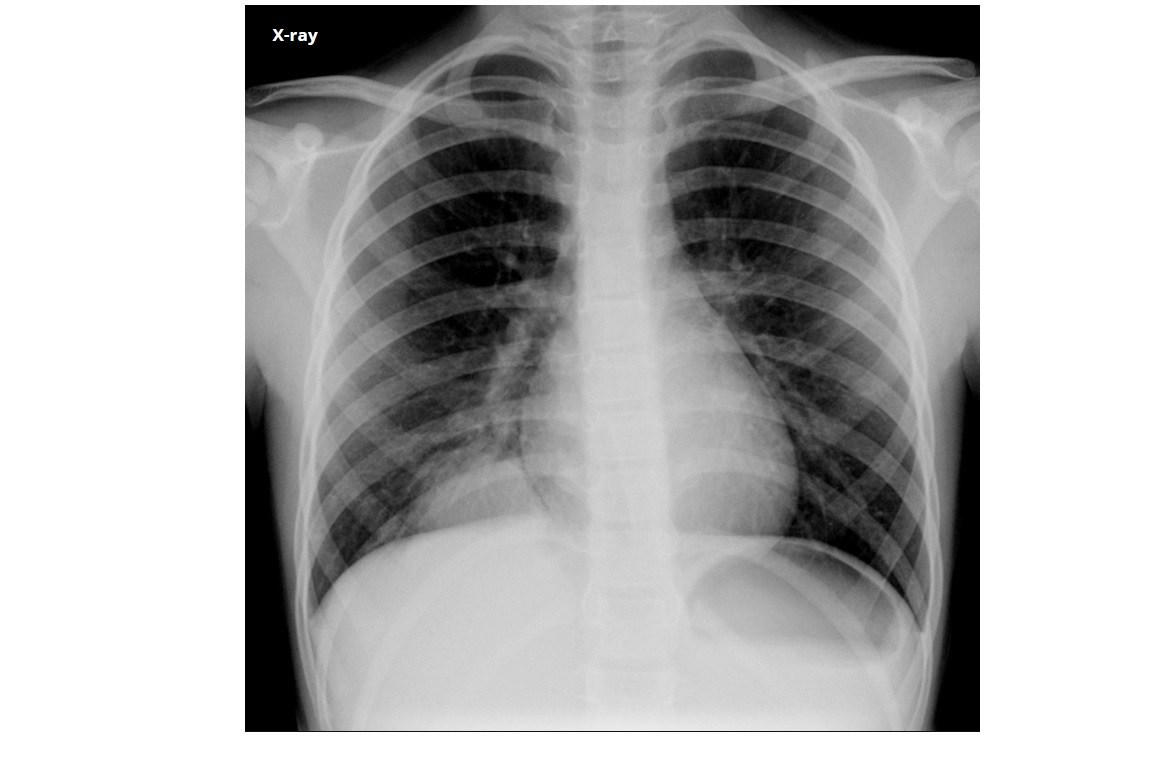

Pulmonary Langerhans cell histiocytosis (PLCH)

Predominant upper lobes

bizarre-shaped thick pulmonary cysts

Smokers

Early stages of disease, 1-10mm nodules in mid/upper zone predominant

Effusions are rare

Sparing costophrenic angles